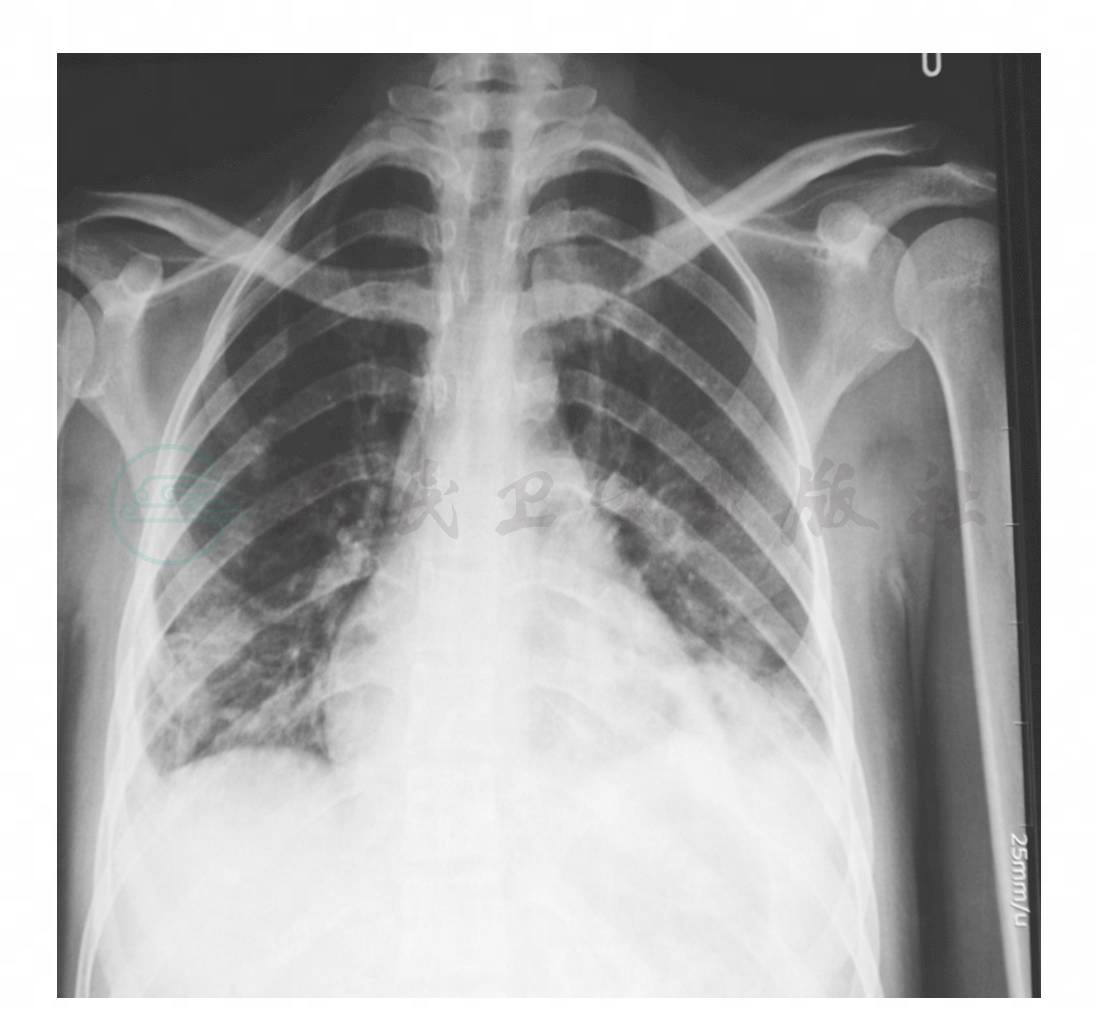

入院查体:T 38.5℃,P 120次/分,身高160cm,体重45kg,消瘦,唇略发绀,手臂有注射针眼,双肺闻及湿鸣音,心率快,胸骨左缘Ⅲ~Ⅳ肋骨间收缩期杂音Ⅲ级,扪及肝于右肋下6cm、剑突下5cm,移动性浊音(-),双下肢无水肿。血:WBC 14.99×109/L,N 90%,Hb 62g/L;肝功能:清蛋白(Alb)20.7g/L,其余正常;肾功能和电解质正常,红细胞沉降率(ESR)87mm/h,梅毒螺旋体抗体阴性,HIV抗体初筛试验阴性。X线胸片和肺部CT检查结果见图1、图2。

图1 胸片(2009-6-2):双下肺炎,双侧胸腔少量积液